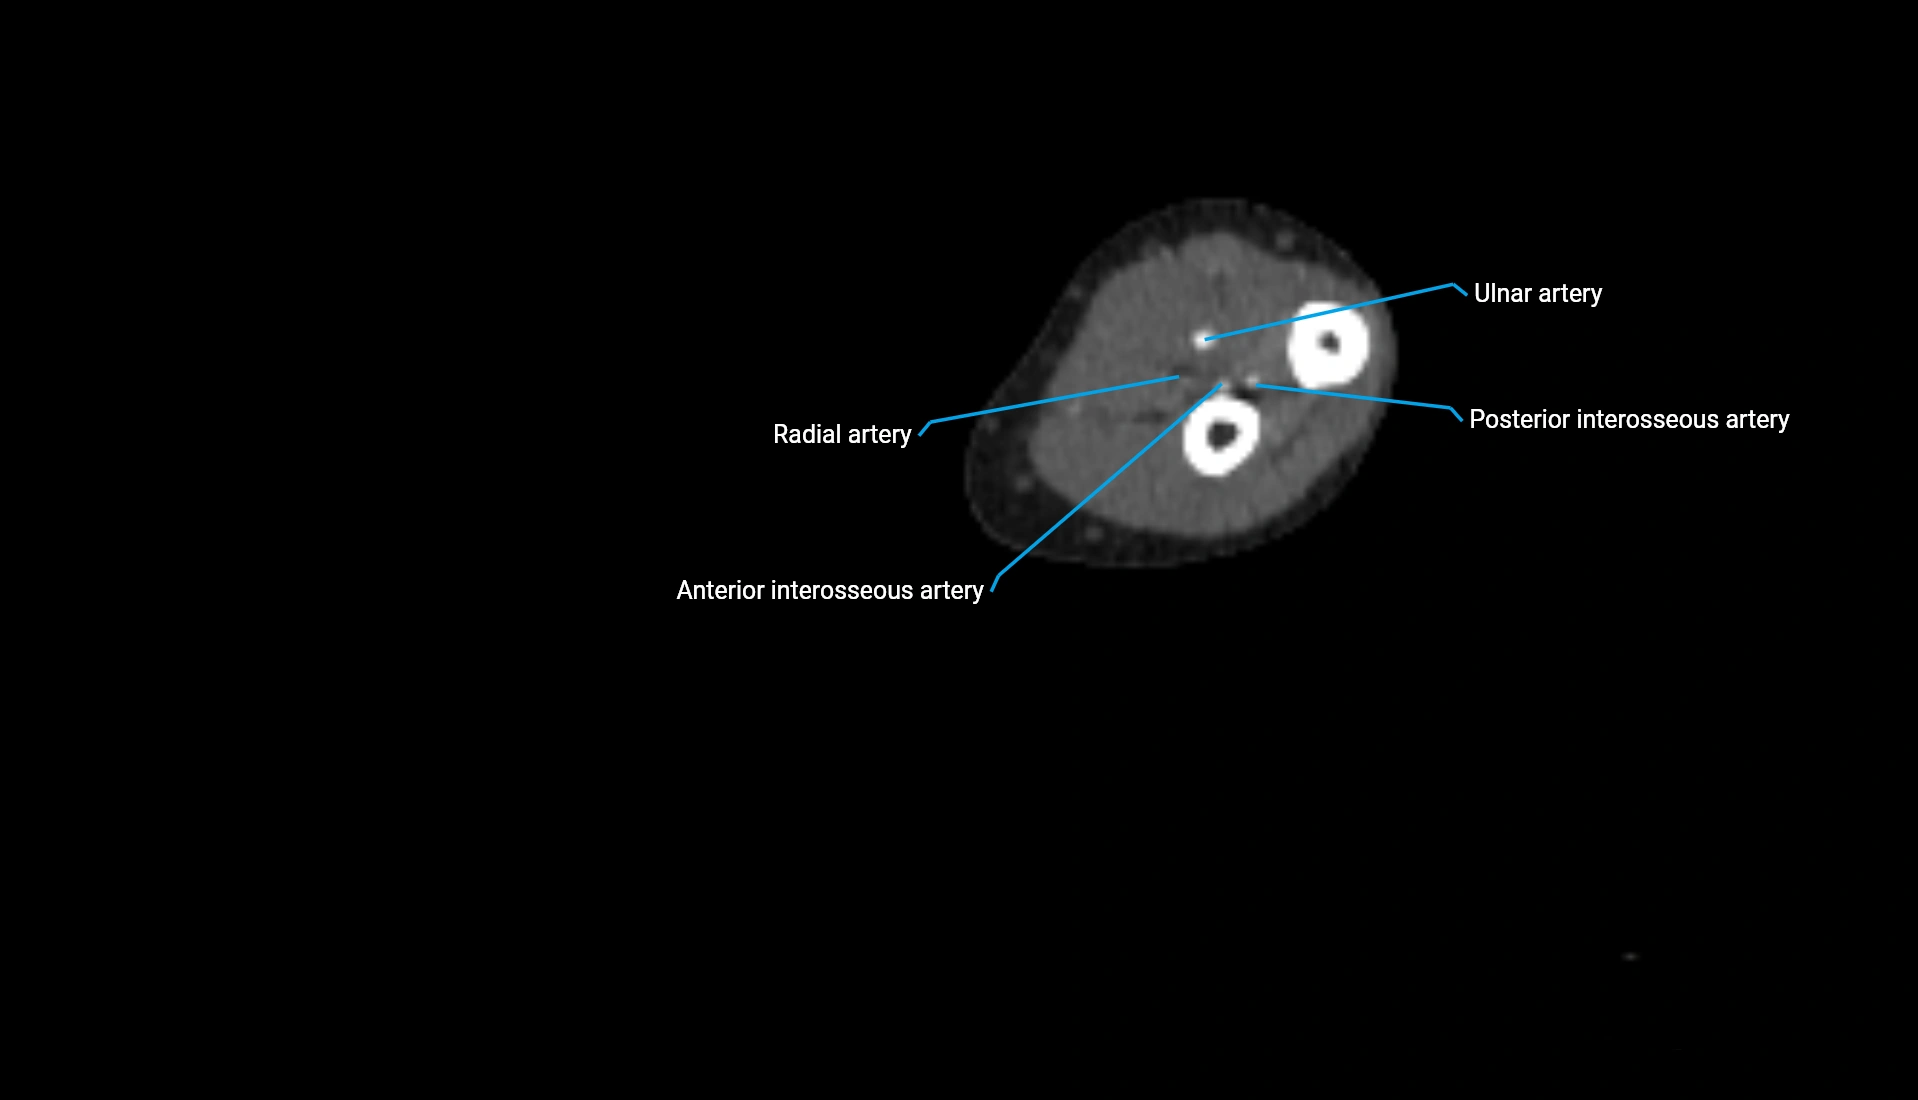

CT Appearance

Non-Contrast CT:

• Cortex: High-density, sharply defined

• Subchondral bone: Dense cancellous matrix

• Articular surface: Smooth concave contour articulating with the capitellum

• Excellent for evaluating bone integrity, alignment, and subtle fractures